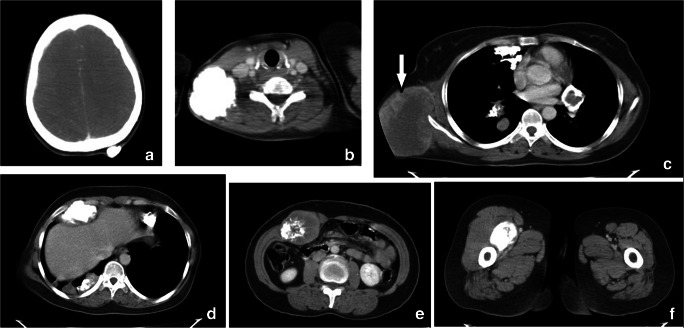

Fig. 2.

CECT scan showing lesions in the (a) occipital scalp, (b) neck, (c) hilar region, pleura based and intraparenchymal lung nodules, right chest wall (arrow), (d) adjacent to liver, (e) anterior abdominal wall, and (f) right upper thigh